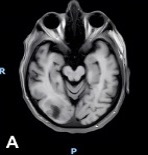

Following the initial brain MRI, a lumbar puncture (LP) performed during hospitalization revealed atypical lymphocytes but no immunophenotypic evidence of lymphoma. A subsequent LP, performed 2 days later, showed persistent pleocytosis without malignant cells. Six days after his initial brain MRI, a follow-up MRI demonstrated extension of the right occipital lesion with leptomeningeal enhancement along ventricular surfaces, brainstem, and cranial nerves (Figure 2A-B), raising continued concern for lymphoma or metastatic disease.

Figure 2A-B. MRI of the brain shows a right occipital lobe lesion extending to the lateral ventricle with abnormal contrast enhancement along ventricular, ependymal, and leptomeningeal surfaces. (A) Axial contrast-enhanced T1-weighted MRI demonstrating an irregular enhancing lesion that is centered in the right occipital lobe, extending toward the occipital horn of the right lateral ventricle. (B) Sagittal T2-weighted FLAIR MRI demonstrating extensive hyperintense signal within the right occipital and posterior parietal white matter that is consistent with vasogenic edema surrounding the lesion with mild local mass effect.